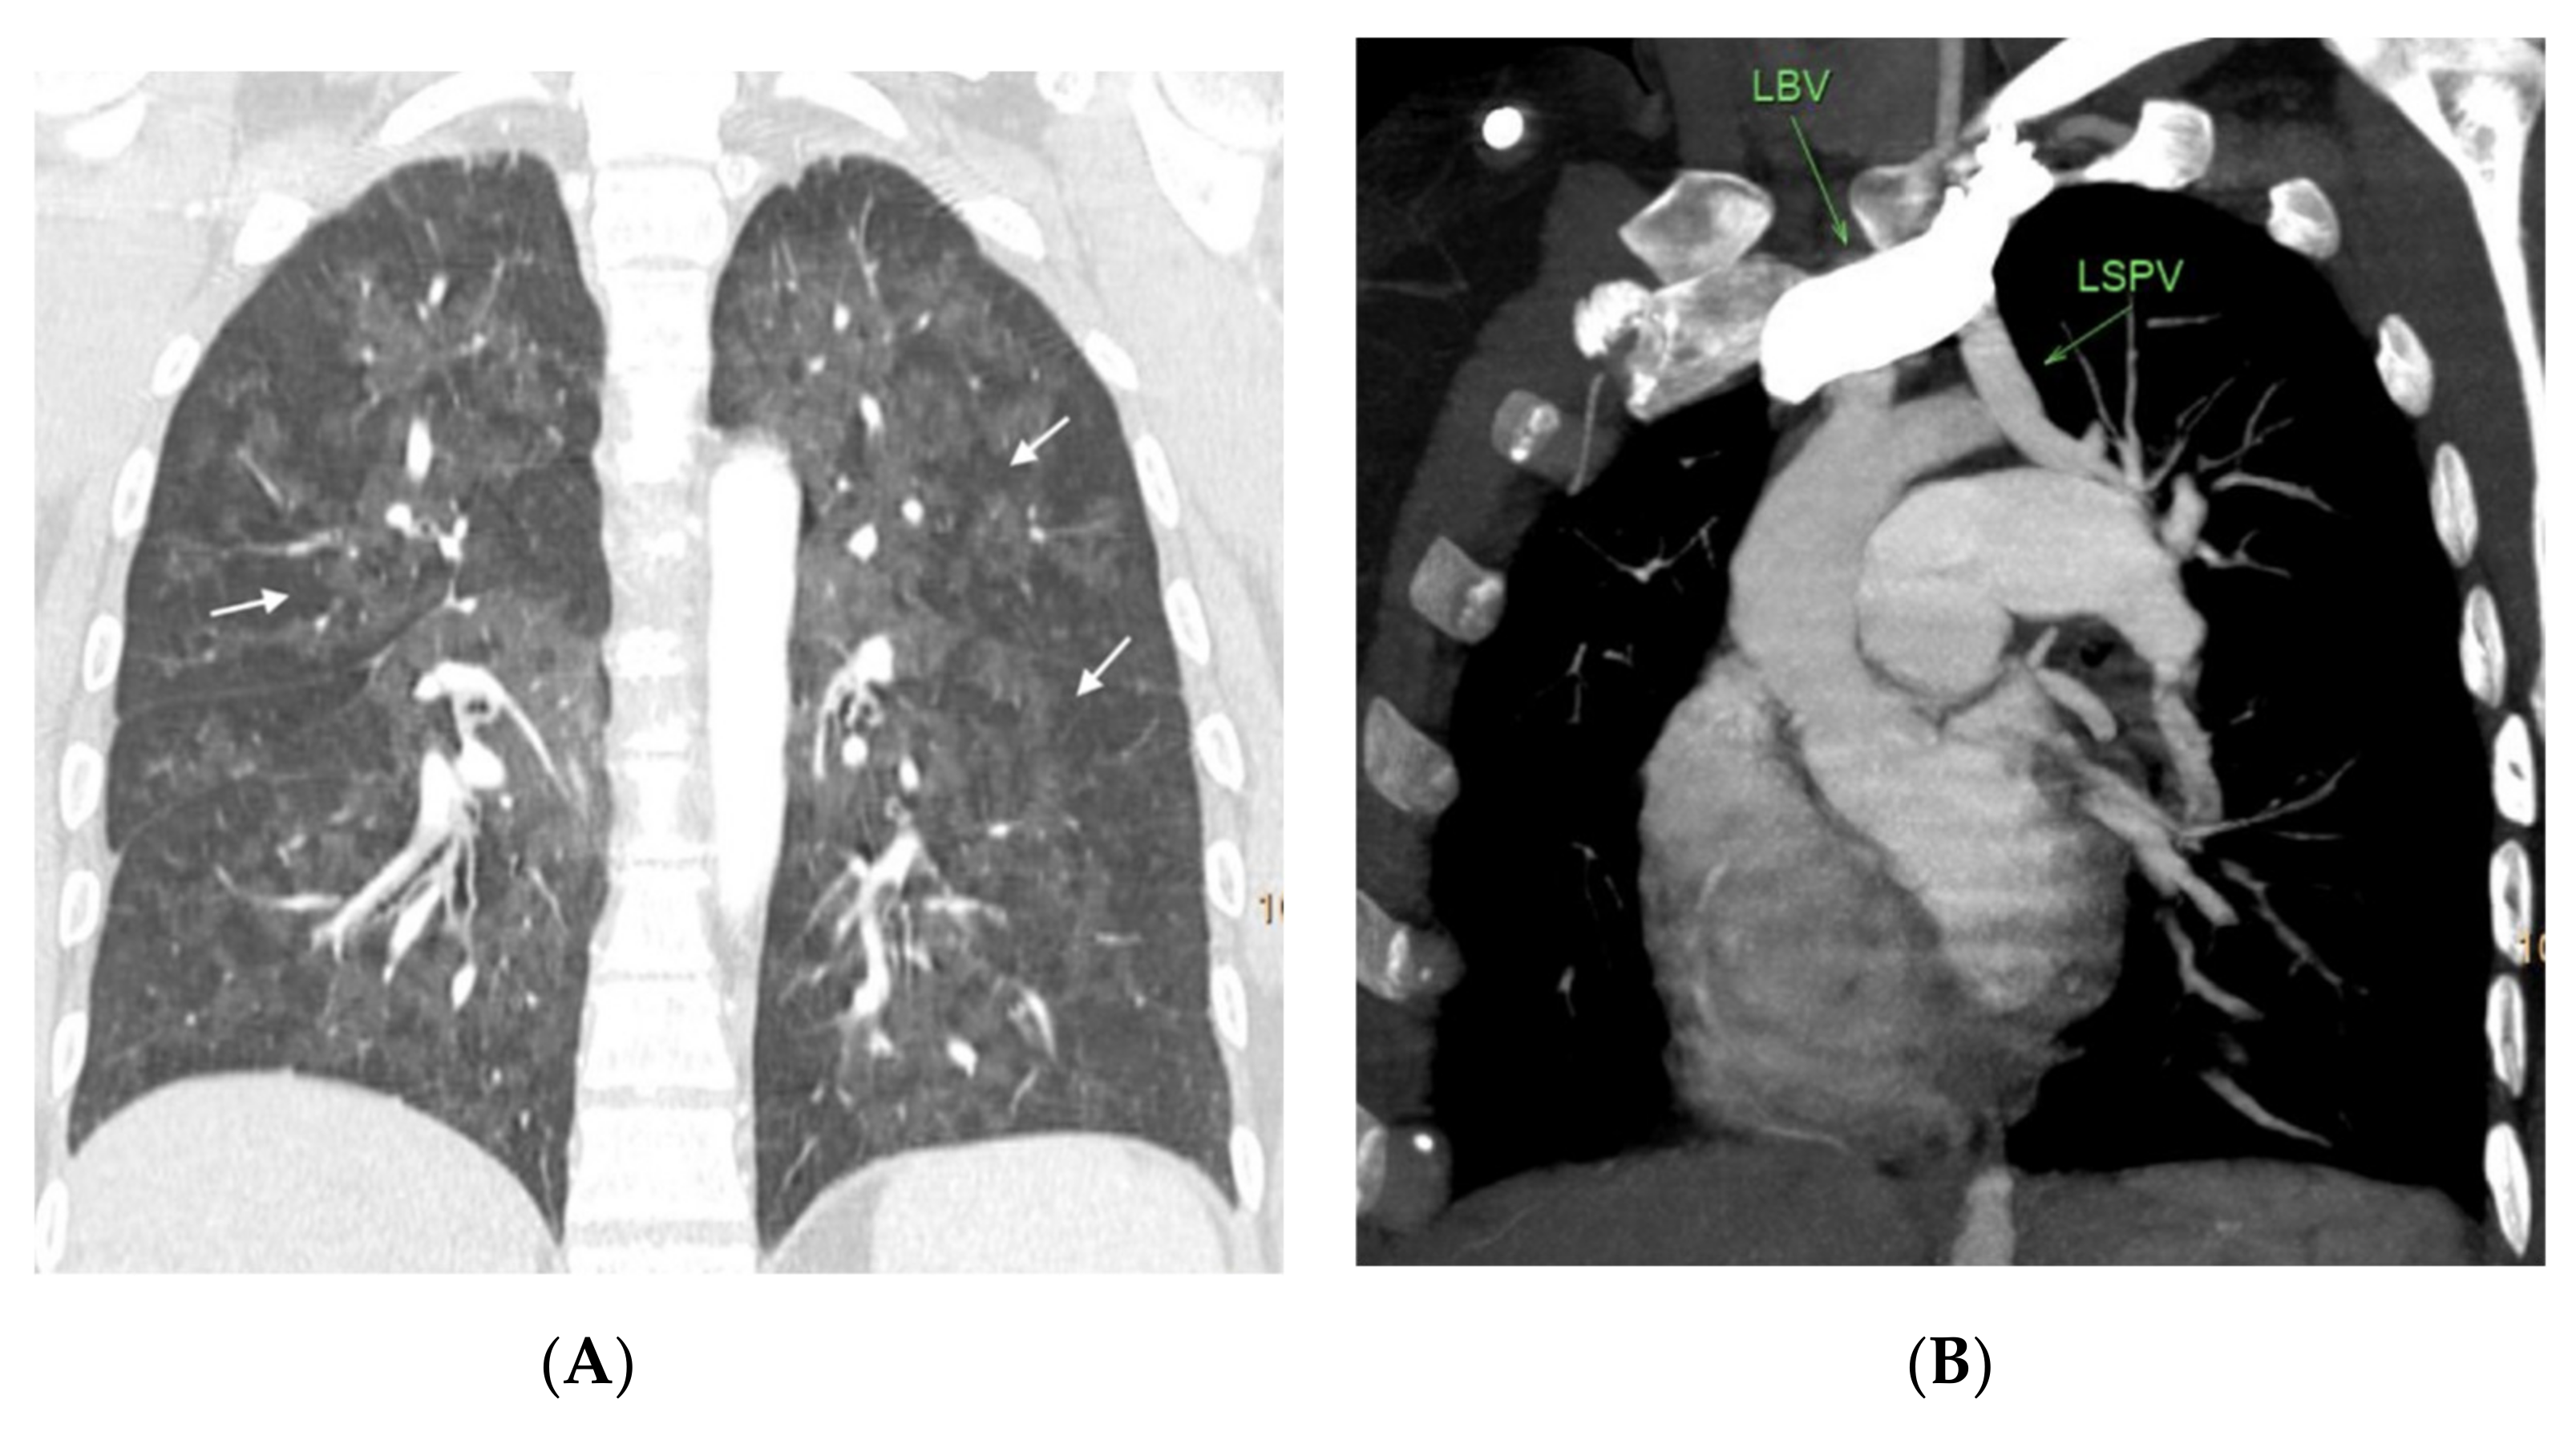

Figure 6.

Nineteen-year-old male with hereditary PVOD and two typical findings. (A) Prevascular and right paratracheal lymphadenopathy (arrows); (B) coronal image. Septal lines in both lower lobes (arrows). There is no ground glass parenchymal involvement.

Figure 7.

Thirty-three-year-old woman with hereditary PVOD with one radiological finding and partial anomalous pulmonary venous drainage. (A) Coronal reconstruction of the lung parenchyma. Extensive ground glass involvement showing geographic distribution (arrows), without evidence of septal lines; (B) oblique multiplanar reconstruction showing the abnormal drainage of the left superior pulmonary vein in the left brachiocephalic venous trunk. LSPV = left superior pulmonary vein. LBV = left brachiocephalic trunk.